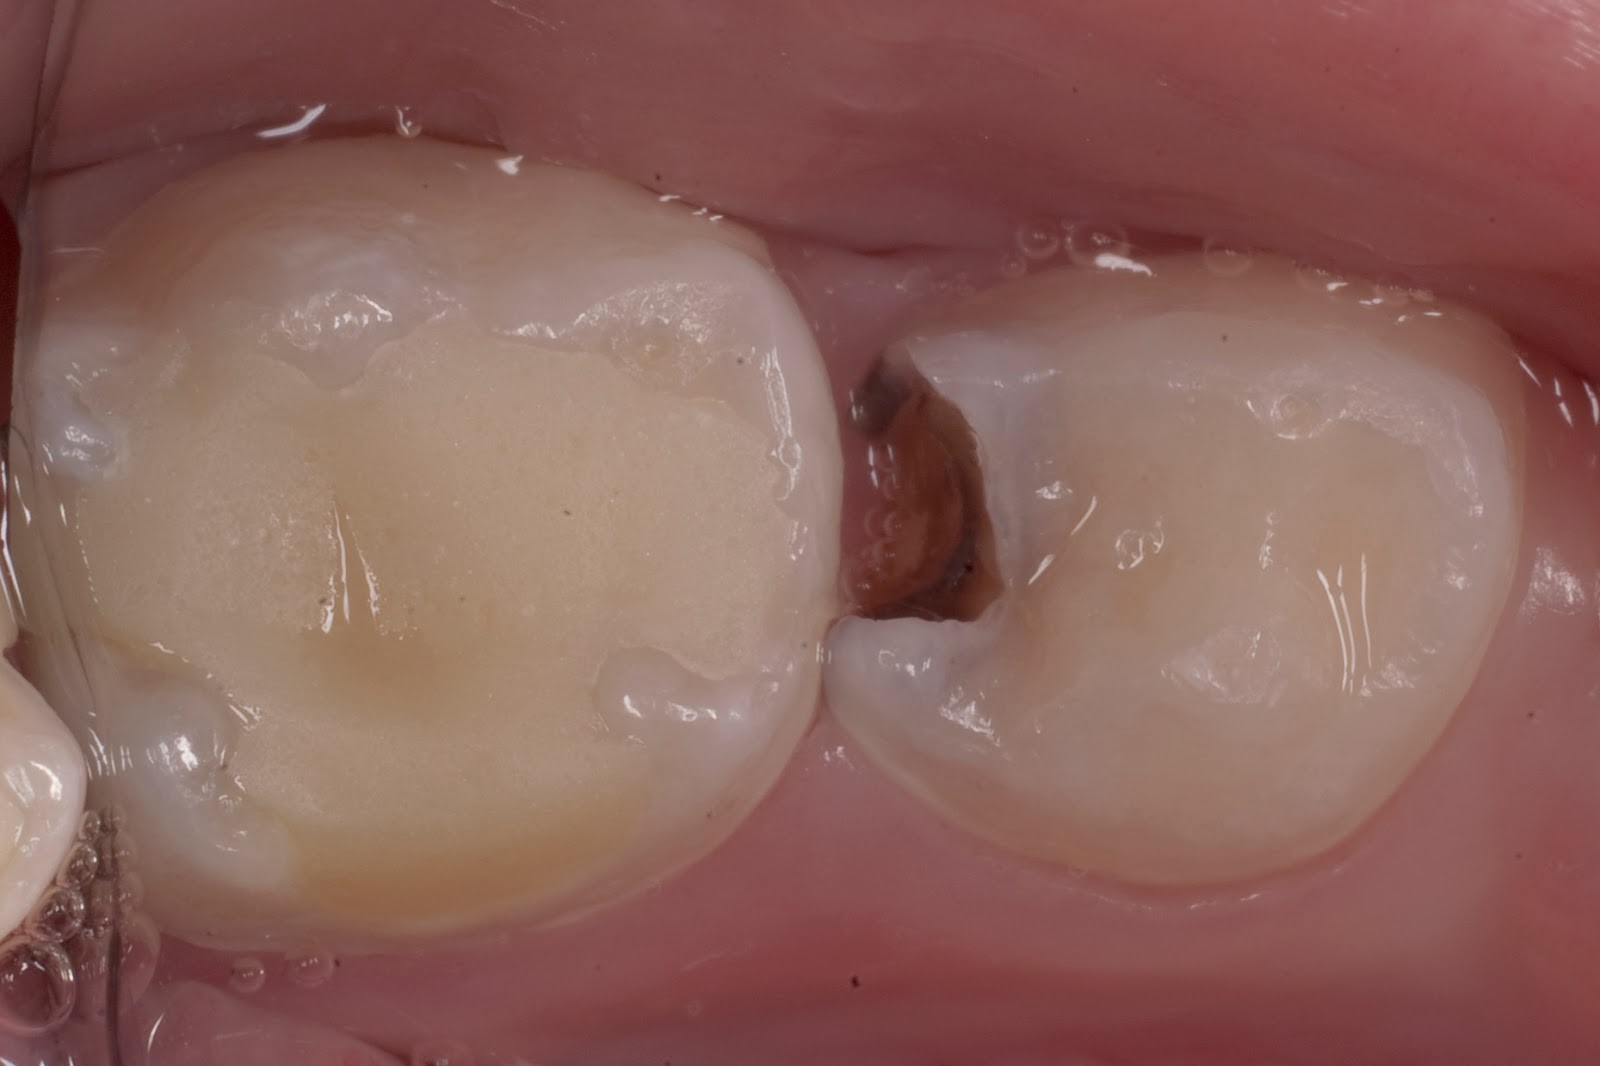

На фотографии кариес, который образовался в фиссурах (бороздки и канавки) зубов.

Различают две основные формы среднего кариеса: хроническую и острую. В первом случае в зубе отчетливо видно большое широкое отверстие с твердыми стенками. Хронический средний кариес протекает без явных клинических проявлений, постепенно переходя в следующую стадию. Чаще всего развивается на жевательных поверхностях зубов. При острой форме, напротив, «дупло» имеет хрупкие края, оно заполнено поврежденным мягким дентином. По своей локализации средний кариес может быть контактным, фиссурным или пришеечным.